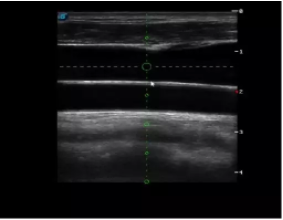

實時觀察穿刺針進入血管的全過程,方便操作及較短的穿刺路徑,智能進針尺寸提示,讓置管工作更加輕松,高效。

不同進針路徑